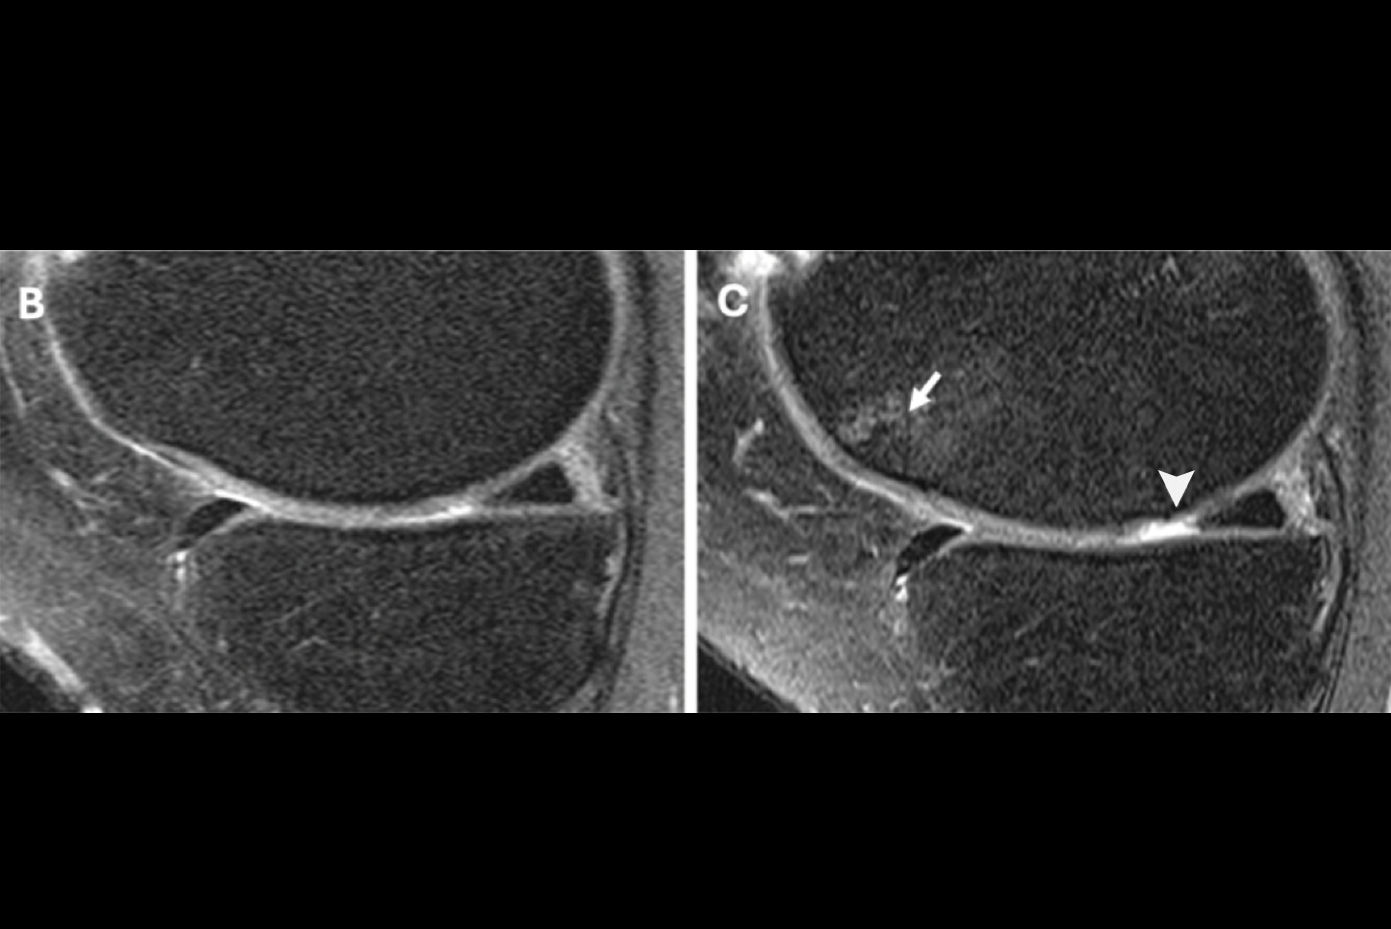

MRI scans of right knee at baseline (A and C) and after 48 months (B and D). Top-row images are of an obese 65-year-old woman with stable weight and mild knee pain; bottom-row images are of an obese 64-year-old woman with weight loss (11% less BMI) over 48 months. The woman with stable weight developed a full-thickness focal cartilage defect at the medial tibia (arrow). In contrast, no cartilage defects were seen in the woman with weight loss. Images courtesy of Radiology."These findings suggest that a larger amount of weight loss is more beneficial for cartilage than is moderate or no weight loss," the authors wrote. "Both weight loss groups showed reduced cartilage degeneration in the medial tibia, which supports the hypothesis that weight loss is most protective for the weight-bearing regions."